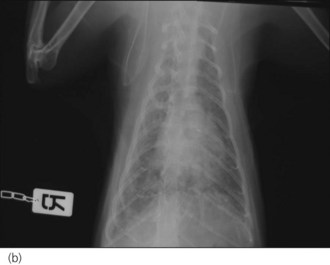

Figure 32.4 Right lateral and dorsoventral thoracic radiographs of a cat with idiopathic chylothorax (a, b) before and (c, d) after thoracocentesis. The post-drainage films were taken the day after under general anaesthesia; an oesophageal stethoscope is visible.